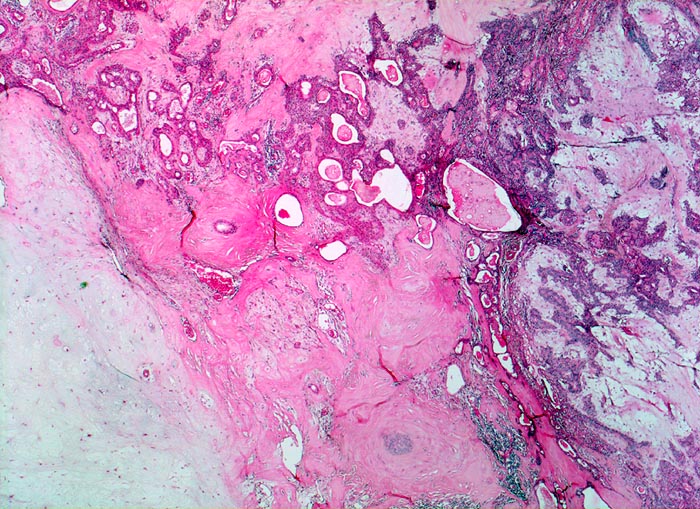

PathoPic ID 3423 - Pleomorphes Adenom der Speicheldrüse

Pleomorphes Adenom der Speicheldrüse

benigner Tumor

Parotis

Kopf & Hals, Sinnesorgane

In dieser Übersichtsaufnahme kommt die Pleomorphie gut zur Darstellung. Innerhalb der unterschiedlich dichten Matrixkomponenten finden sich drüsenbildende

epitheliale Komponenten.

5cm grosser bekapselter Tumor in der linken Parotis.

Schmerzlose Vergrösserung der Parotis.

Histologie

25